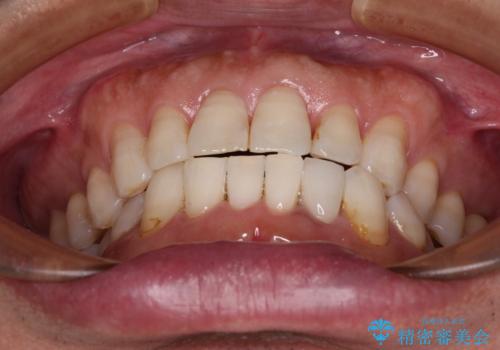

内側にある歯が干渉する 上顎前歯の部分矯正

セラミッククラウンとの干渉はすぐに改善され、歯列も整いましたが、一方で、前歯で食事が噛みにくくなり、1年近い治療期間となりました。